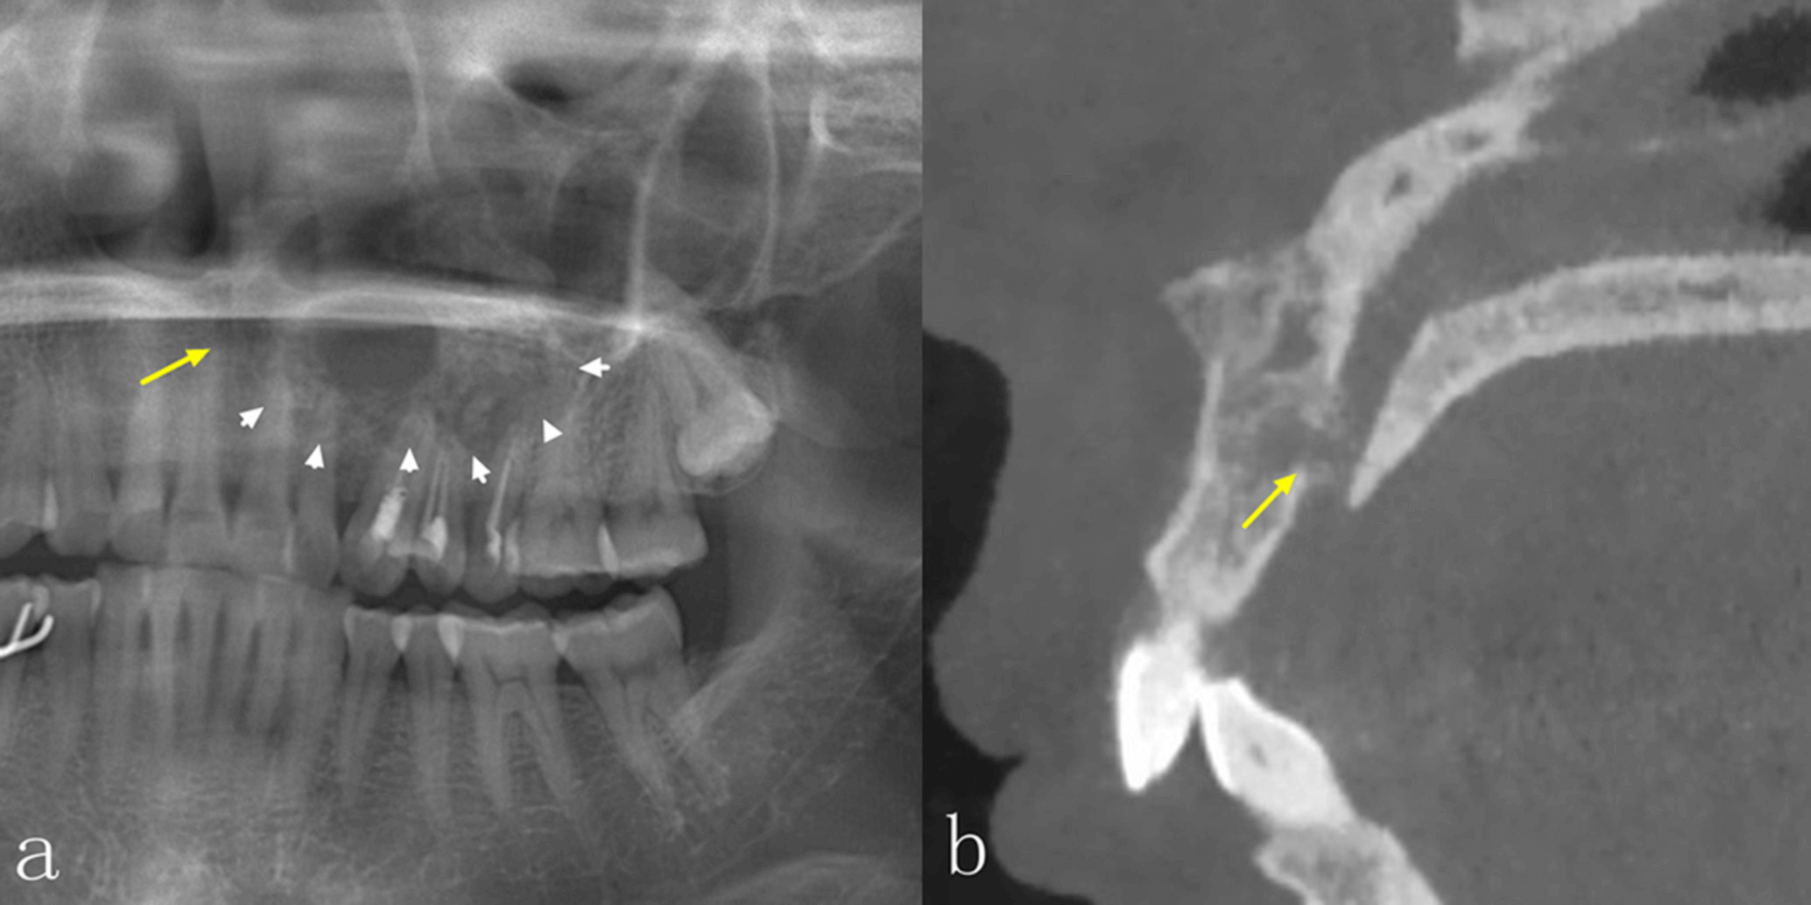

La radiografía panorámica (PAN) y la tomografía computarizada de haz cónico (TCCB) son dos modalidades radiográficas utilizadas en el diagnóstico, la planificación del tratamiento y el manejo de las enfermedades orales y maxilofaciales. No solo muestran las características de las lesiones en las imágenes, sino que también guían a los médicos para que realicen los diagnósticos más adecuados, así como los planes de tratamiento posteriores, y para supervisar la curación y/o la recurrencia de la enfermedad durante el seguimiento. La PAN, como técnica de imagen más común, puede proporcionar una visión general de las mandíbulas y la dentición, pero las estructuras anatómicas y las lesiones en las mandíbulas anteriores no están bien definidas debido a la superposición de las vértebras cervicales. Además, la calidad de la imagen de la PAN puede verse influenciada por la superposición de las estructuras anatómicas circundantes, las sombras de aire, las imágenes fantasmas y la sensibilidad a los errores de posicionamiento del paciente. Estos errores también darán lugar a una distorsión de la imagen y a un aumento desigual en las dimensiones horizontal y vertical. La CBCT, que se ha introducido ampliamente en la imagenología maxilofacial desde finales de la década de 1990, tiene ventajas sobre la PAN bidimensional PAN bidimensional, debido a su naturaleza tridimensional. La CBCT no solo muestra las estructuras anatómicas y las lesiones en los planos axial, coronal y sagital, sino que también permite realizar una variedad de efectos de posprocesamiento.

Es bien sabido que la TCCB presenta numerosas ventajas en el diagnóstico de enfermedades orales y maxilofaciales. En comparación con la PAN, la TCCB puede proporcionar más información para ayudar a los odontólogos a realizar diagnósticos, diseñar planes de tratamiento y supervisar los seguimientos postoperatorios. Actualmente, hay una escasez de estudios que se centren en las diferencias de las características radiográficas entre la PAN y la TCCB para obtener imágenes de las lesiones intraóseas de la mandíbula mediante un método cuantitativo. El estudio más reciente, con 31 casos incluidos, mostró que, aunque había diferencias en el aspecto radiográfico de las lesiones intraóseas en la PAN y la TCCB, la TCCB no ayudaba a mejorar la precisión del diagnóstico. Los autores concluyeron que el bajo número de casos de su estudio era una limitación. Por lo tanto, los objetivos de este estudio, que utilizó un mayor número de lesiones, fueron: investigar las diferencias en las características de imagen de las lesiones intraóseas de la mandíbula entre PAN y TCCB; y determinar con mayor precisión la eficacia diagnóstica de las dos modalidades radiográficas en la evaluación de las lesiones intraóseas de la mandíbula.

Las diferencias significativas en el aspecto radiográfico de las lesiones intraóseas entre la PAN y la TCCB se observaron en la integridad de los bordes corticales, la expansión de los límites anatómicos circundantes, el adelgazamiento cortical, la destrucción cortical y la reabsorción radicular, especialmente en las regiones anteriores de ambos maxilares y en el maxilar superior. La TCCB también mejoró la precisión diagnóstica, especialmente en las lesiones del maxilar superior. Los radiólogos se mostraron más seguros al utilizar TCCB en comparación con PAN. Estos hallazgos podrían utilizarse en el desarrollo de directrices para la obtención de imágenes de patologías intraóseas en los maxilares.